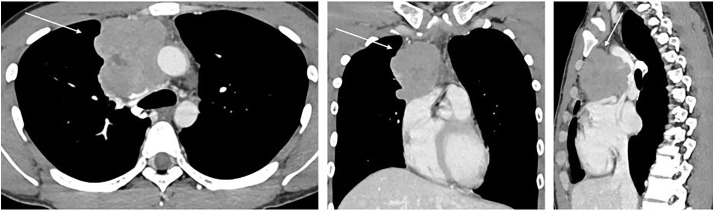

Case presentation: The patient was a 25-year-old man who had been experiencing labored breathing when leaning forward for the past month. Physical examination revealed distended jugular veins and neck edema. Chest computed tomography revealed an irregular mass measuring 80 mm in the anterior mediastinum, suggesting invasion of the superior vena cava. Additionally, fluorodeoxyglucose-positron emission tomography showed high accumulation in the same area, with a maximum standardized uptake value of 11.3. A tumor biopsy was performed under thoracoscopic guidance for definitive diagnosis. Histopathological examination of the resected specimen revealed a seminoma with granulomatous changes. Based on these findings, a diagnosis of anterior mediastinal seminoma with superior vena cava syndrome was made. It was classified as having a good prognosis, and the patient received three courses of induction chemotherapy with etoposide, cisplatin, and ifosfamide. Complete remission was achieved. Since then, the patient has been monitored every 3 months, with no recurrence or metastasis observed for approximately 2 years.